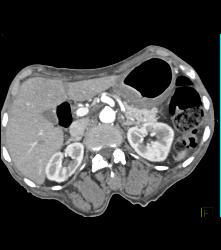

Gastric Adenocarcinoma With Celiac Nodes